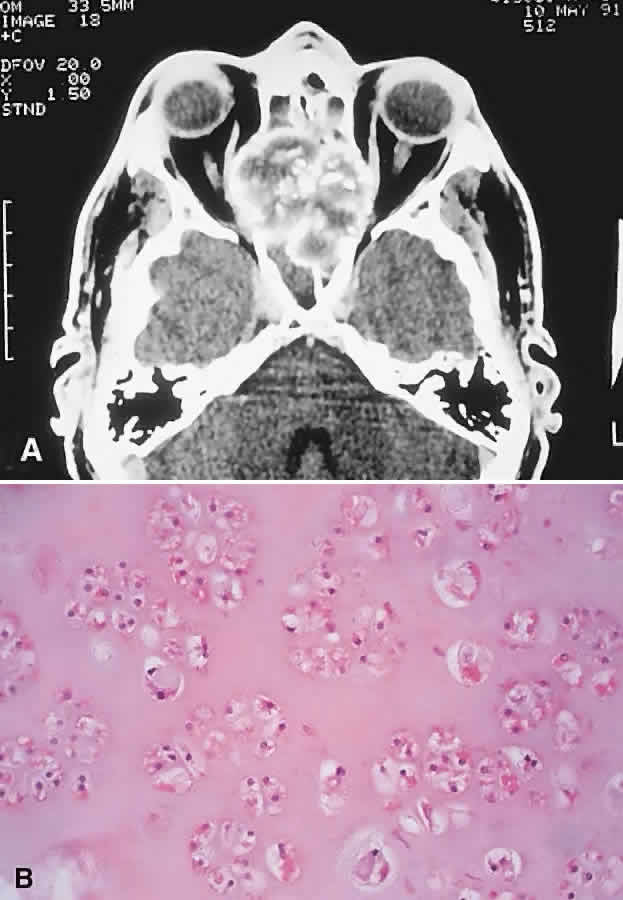

PRESENTATION. A superolateral mass effect encompassing weeks to years is the typical mode of presentation. This leads to inferior globe displacement, proptosis, and diplopia in upgaze (Fig. 5). There may be associated headache or pain; one third of patients recall a prior trauma.70,71

Fig. 5. A 41-year-old man had a 2-year history of left proptosis and headaches. A. Examination found 6 mm of proptosis with 4 mm of inferior ocular displacement. B. CT showed an osteolytic mass arising from the superolateral frontal bone and extending into the orbit. C. Histologically, a classic picture of cholesterol granuloma was apparent, with numerous cholesterol clefts surrounded by granulomatous inflammation containing foreign body giant cells (hematoxylineosin, × 20).

IMAGING. The granuloma arises in the diploë of the frontal bone, causing expansion and eventually erosion of the inner and outer tables. CT reveals it to be osteolytic, with a density equivalent to brain, and occasional intralesional bone fragments.72 Mature lesions display high T1 and T2 signal intensities on MRI.73,74 The most commonly evoked differentials in this setting are dermoid cysts and lacrimal gland carcinomas.

HISTOPATHOLOGY. These cysts usually contain yellow-brown viscous material with friable tissue and porous bone at the periphery. Histologically, the principal feature is the dominance of cholesterol clefts surrounded by granulomatous inflammation with conspicuous foreign body giant cells. A variable fibrous stroma is present and usually contains extensive blood-derived debris in the form of extracellular and intracellular hemosiderin as well as more recent hemorrhage.70,75